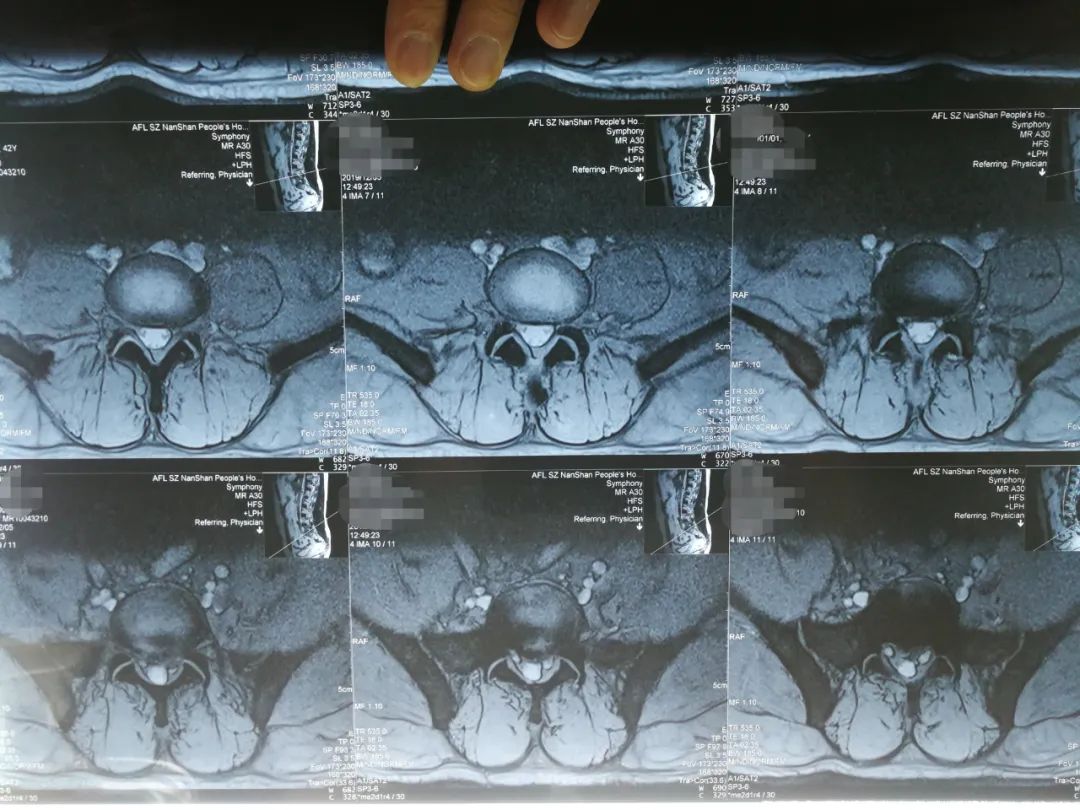

阅片

刘先生是典型的“腰椎间盘突出症(L5S1左后突出)”,伴有椎管狭窄的间歇性跛行症状,专科查体时最主要的体征是:

1、L5S1棘突左侧旁开1厘米处压痛、叩击痛并反射至左小腿后侧(骶1神经支配区);

3、左侧跟腱反射消失(骶1神经受压所致)。